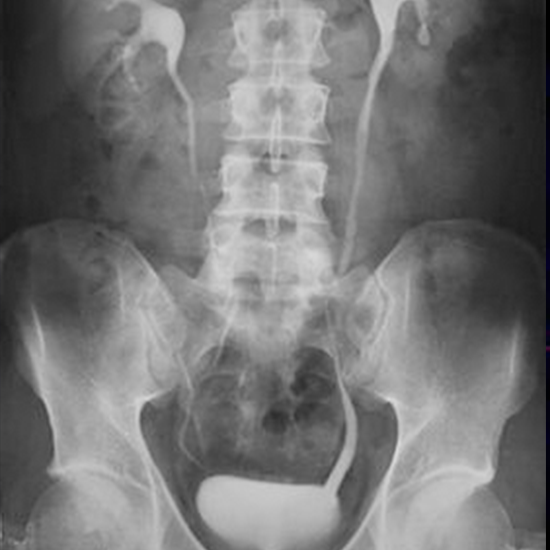

The imaging procedure known as intravenous urography (IVU), commonly referred to as intravenous pyelography (IVP), is used to check the kidney, ureters (the tiny tube that transports urine to the urinary bladder), and the urinary bladder. Monitoring is done of the passage of a contrast dye from the vein through the kidney to the urine bladder.

• The patient has to lie in the supine position and take a scout image.